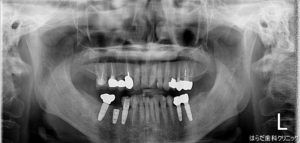

右下5番 インプラント一次オペ

本日一件のインプラントの一次オペが行われました。

右下の5番目の歯茎にインプラントを埋入しました。